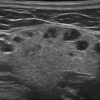

Hạch tuyến nước bọt

» Thông tin: Nữ giới – 66 tuổi.

» Lâm sàng: Sưng đau vùng góc hàm.

# Hạch lành tính ngoại vi tuyến nước bọt dưới hàm.